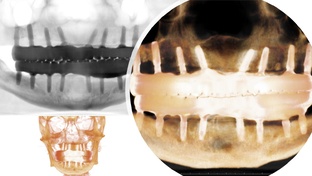

Ну что мы все про ортодонтию? Прикус, брекеты. Удалять не удалять. Скучно же). Давайте про импланты (ну или имплантанты). Удалять будем ВСЁ!)) Мужчина средних лет, крепкого телосложения. Ладно скроен, крепко сшит! НО! Нет половины зубов. А те что есть,- участвуют в акте дыхания! В смысле? В смысле все подвижны как клавиши у пианино. Потеря костной ткани! Это результат пародонтита, которым взрослых по телевизору пугают. (Серенькое на рисунке выше - это кость и в ней зубы. А темненькое - это воздух!)...